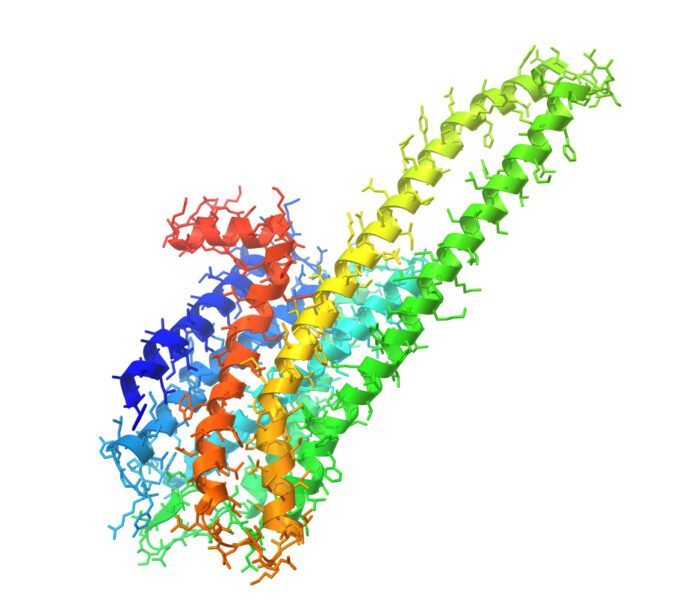

5-ht2a

The 5-HT2A receptor is an important serotonin receptor concentrated in the brain’s prefrontal cortex but also located in the digestive system and throughout the body.

When psychedelics stimulate this receptor, two significant things happen.

One, the production of brain-derived neurotrophic factors increases, stimulating neuronal growth, connections, and activity. Second, the transmission of glutamate, which is responsible for cognition, learning, and memory, is increased throughout the brain.

Human 5-hydroxytryptamine (serotonin) receptor